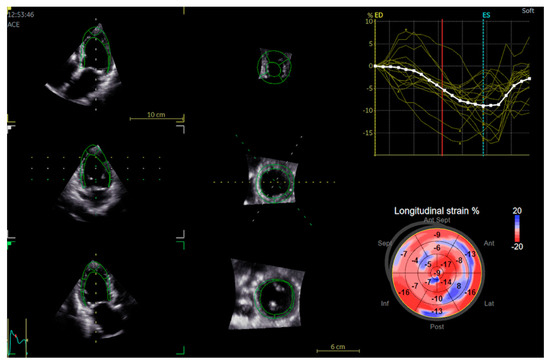

2.2. Echocardiography